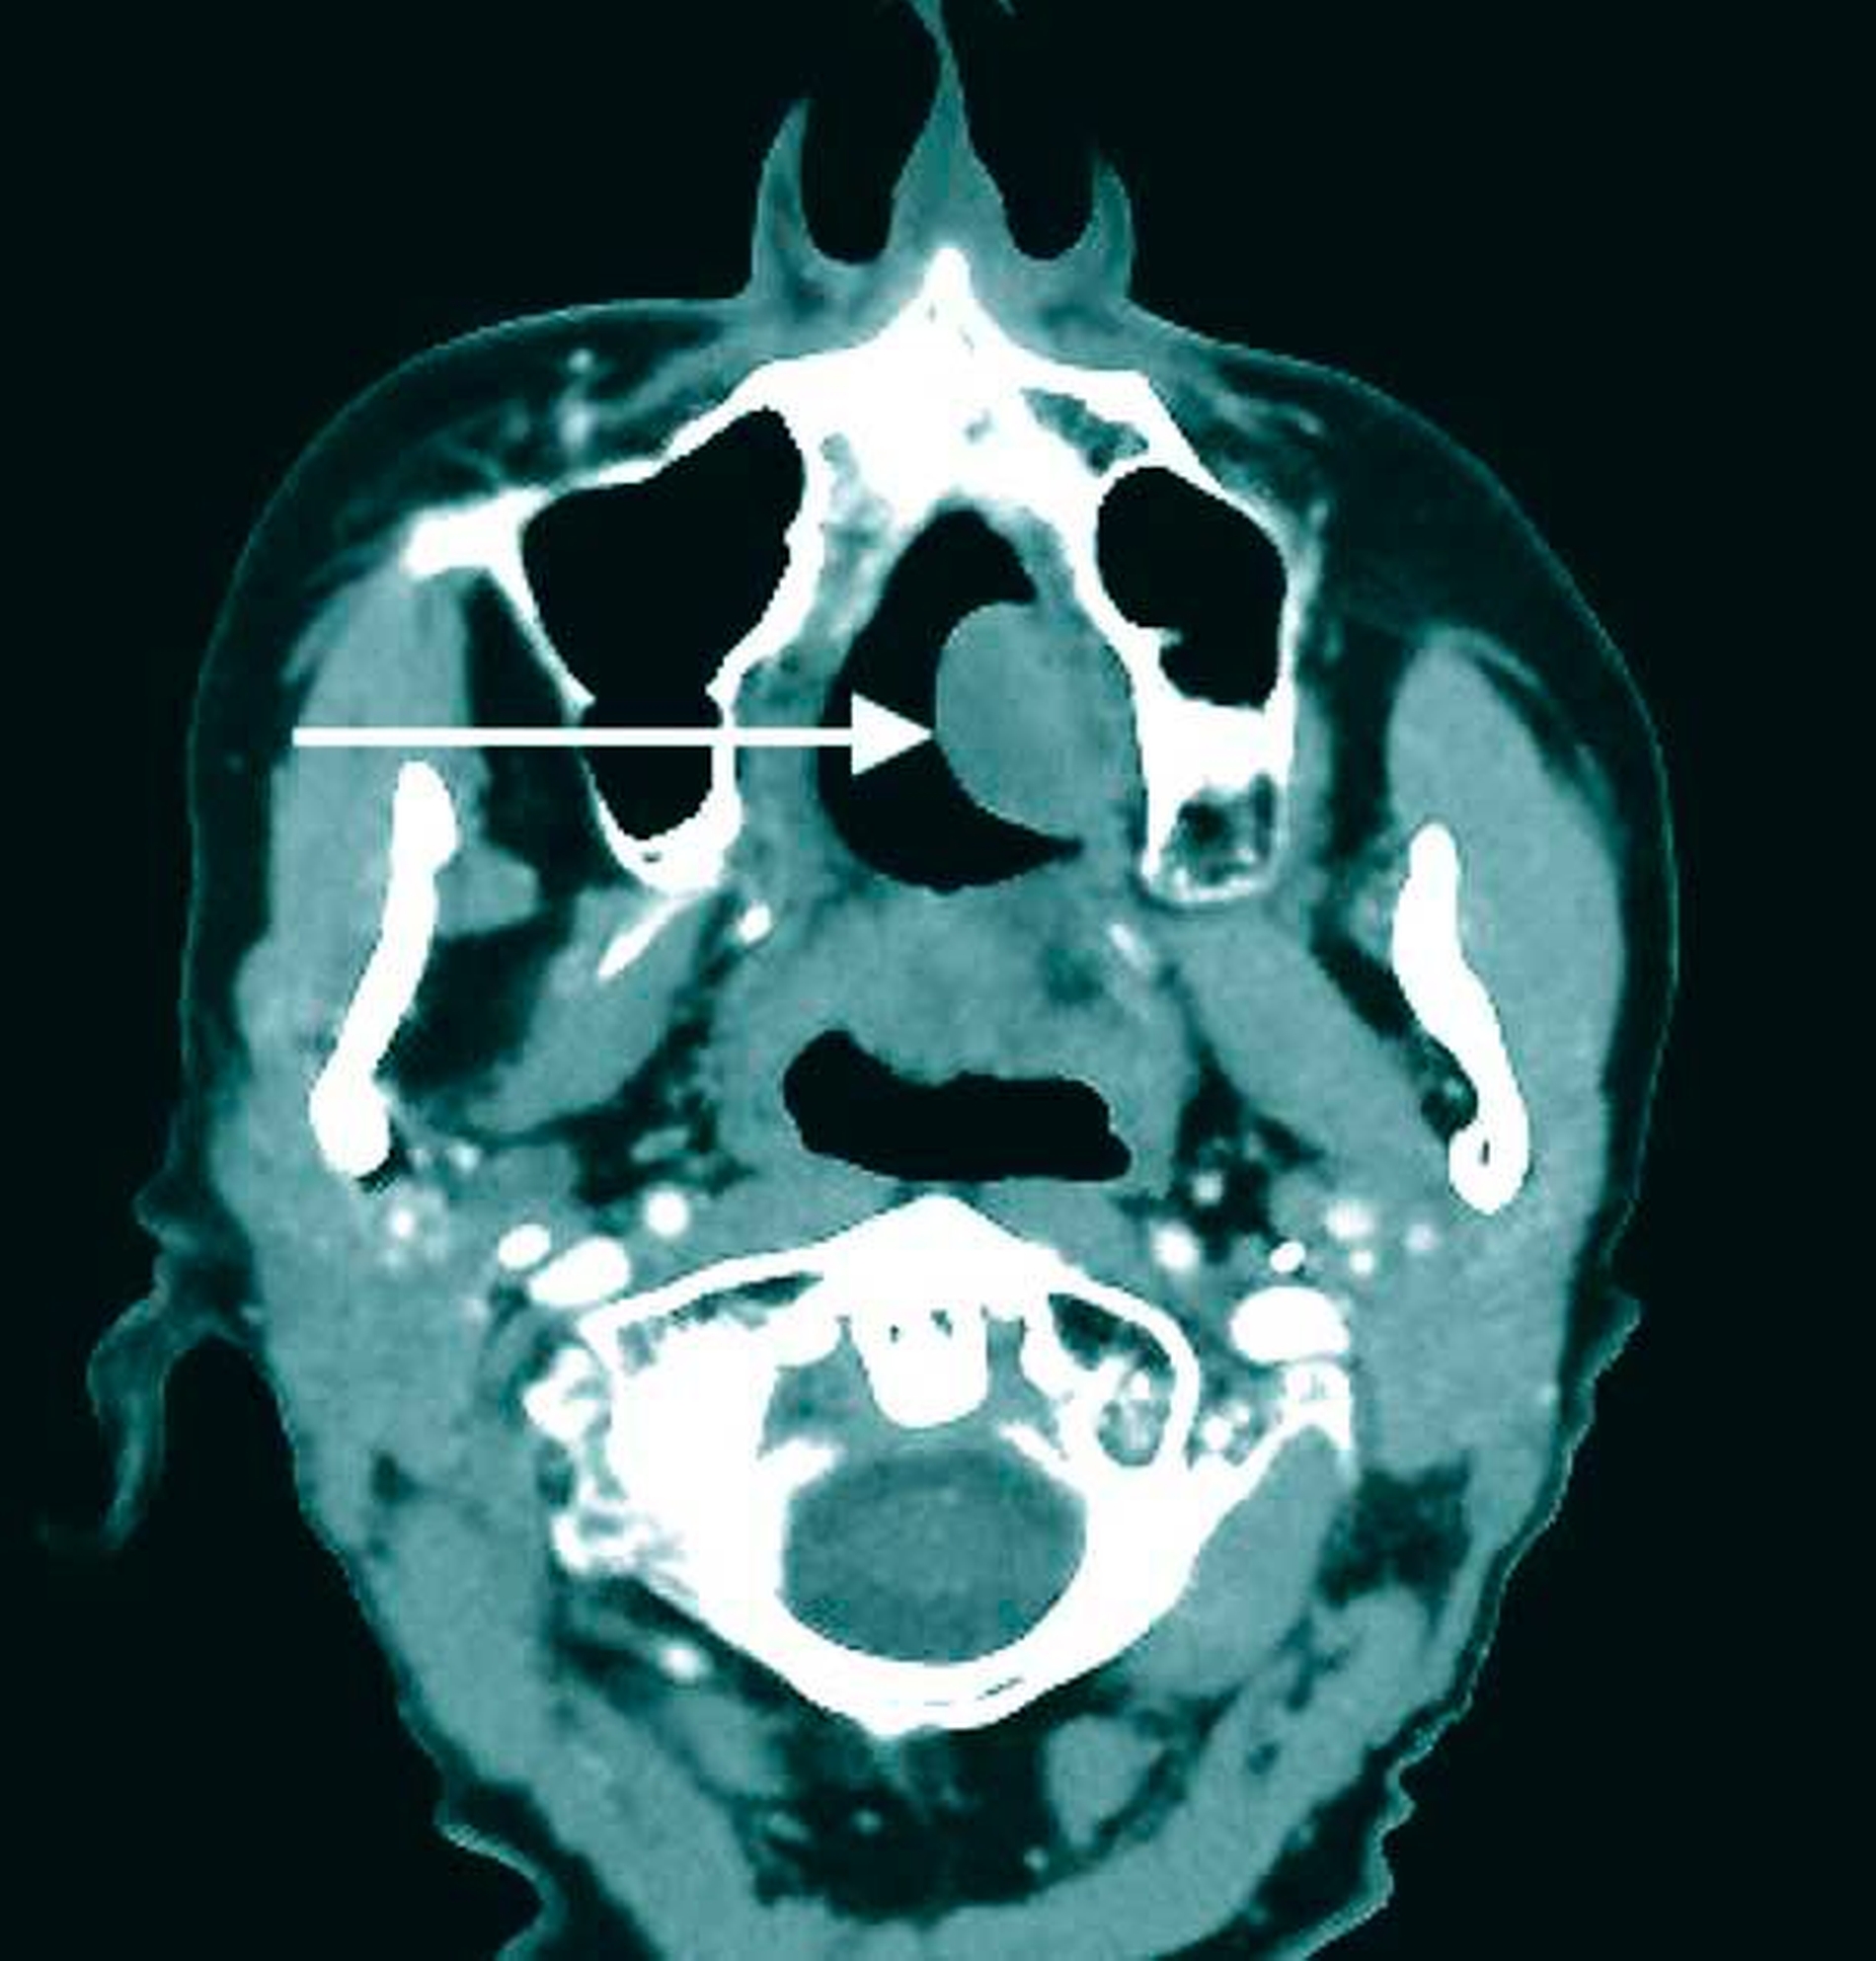

Zur Komplettierung der Diagnostik und zur Darstellung der Tiefenausdehnung des intraoralen Befunds in die angrenzenden Nachbarstrukturen erfolgte ein Kontrastmittel-gestütztes CT der Kopf-Hals-Region (Abbildungen 2a und 2b).

Weiter ist die Durchführung schnittbildgebender Verfahren (Kontrastmittel-CT oder MRT) ein wichtiges Diagnostikum, um eine Infiltration von Nachbarstrukturen auszuschließen, was wiederum das therapeutische Vorgehen beeinflusst [Kinoshita et al., 2016]. Im Fall des polypösen Mundschleimhautfibroms ist eine Spontanremission nicht zu erwarten, so dass die lokale Exzisionstherapie ohne Sicherheitsabstand mit histopathologischer Nachuntersuchung das Verfahren der Wahl darstellt [Mishra and Pandey, 2016].